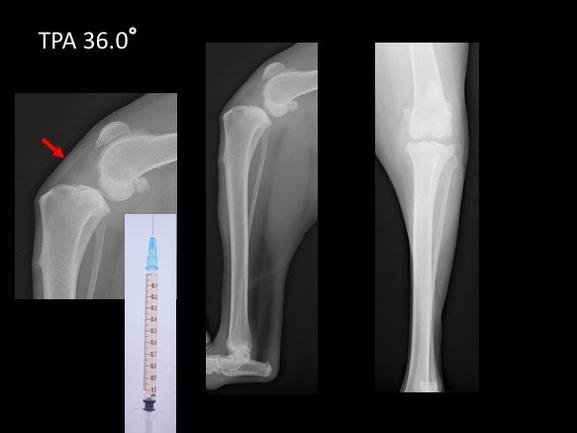

脛骨高平部角(TPA)が35°以上あるものは、傾斜角度がきつく、E-TPAといわれています。まるちゃんはTPAが36°でしたので、目標とする角度に矯正するには、骨片をかなり回転させることになります。E-TPAは骨同士の接触面積も少なくなるため,正確な整復とインプラントの設置が求められます。